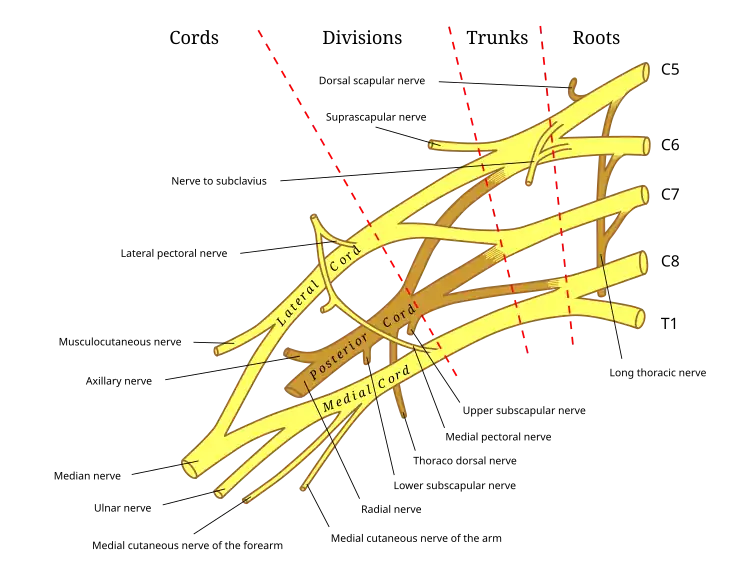

In a radiculopathy, the problem occurs at or near the root of the nerve, shortly after its exit from the spinal cord. However, the pain or other symptoms often radiate to the part of the body served by that nerve. For example, a nerve root impingement in the neck can produce pain and weakness in the forearm. Likewise, an impingement in the lower back or lumbar-sacral spine can be manifested with symptoms in the foot.

Radiculopathy is a diagnosis commonly made by physicians in primary care specialties, orthopedics, physiatry, and neurology. The diagnosis may be suggested by symptoms of pain, numbness, paresthesia, and weakness in a pattern consistent with the distribution of a particular nerve root, such as sciatica.[6][7] Neck pain or back pain may also be present. Physical examination may reveal motor and sensory deficits in the distribution of a nerve root. In the case of cervical radiculopathy, Spurling's test may elicit or reproduce symptoms radiating down the arm. Similarly, in the case of lumbosacral radiculopathy, a straight leg raise maneuver or a femoral nerve stretch test may demonstrate radiculopathic symptoms down the leg.[3] Deep tendon reflexes (also known as a stretch reflex) may be diminished or absent in areas innervated by a particular nerve root.

If symptoms do not improve after 4–6 weeks of conservative treatment, or the person is more than 50 years old, further tests are recommended.[3] The American College of Radiology recommends that projectional radiography is the most appropriate initial study in all patients with chronic neck pain.[13] Two additional diagnostic tests that may be of use are magnetic resonance imaging and electrodiagnostic testing. Magnetic resonance imaging (MRI) of the portion of the spine where radiculopathy is suspected may reveal evidence of degenerative change, arthritic disease, or another explanatory lesion responsible for the patient's symptoms. Electrodiagnostic testing, consisting of NCS (nerve conduction study) and EMG (electromyography), is also a powerful diagnostic tool that may show nerve root injury in suspected areas. On nerve conduction studies, the pattern of diminished compound muscle action potential and normal sensory nerve action potential may be seen given that the lesion is proximal to the posterior root ganglion. Needle EMG is the more sensitive portion of the test, and may reveal active denervation in the distribution of the involved nerve root, and neurogenic-appearing voluntary motor units in more chronic radiculopathies. Given the key role of electrodiagnostic testing in the diagnosis of acute and chronic radiculopathies, the American Association of Neuromuscular & Electrodiagnostic Medicine has issued evidence-based practice guidelines, for the diagnosis of both cervical and lumbosacral radiculopathies.[14][15] The American Association of Neuromuscular & Electrodiagnostic Medicine has also participated in the Choosing Wisely Campaign and several of their recommendations relate to what tests are unnecessary for neck and back pain.[16]